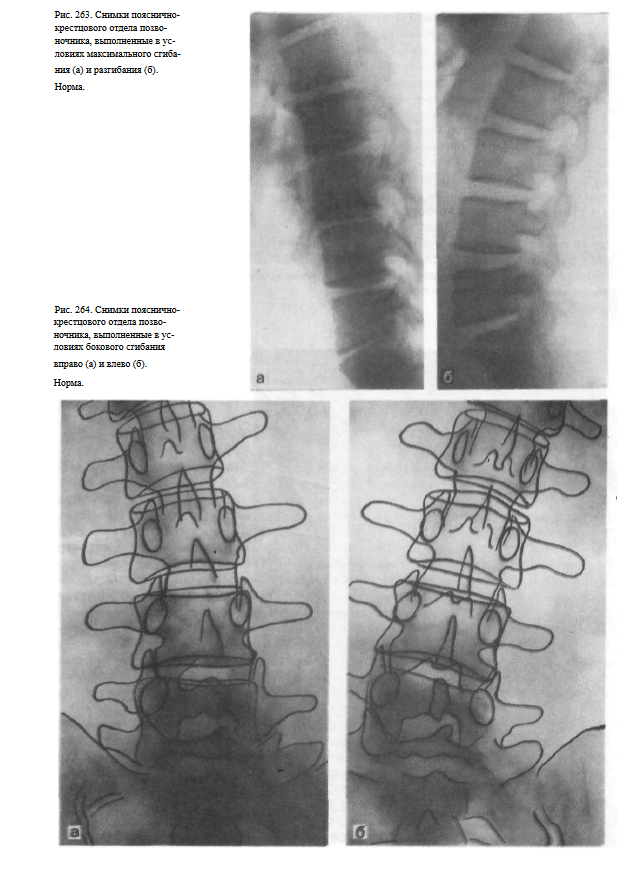

Функциональная проба поп

Функциональная проба поп 86 фотографий